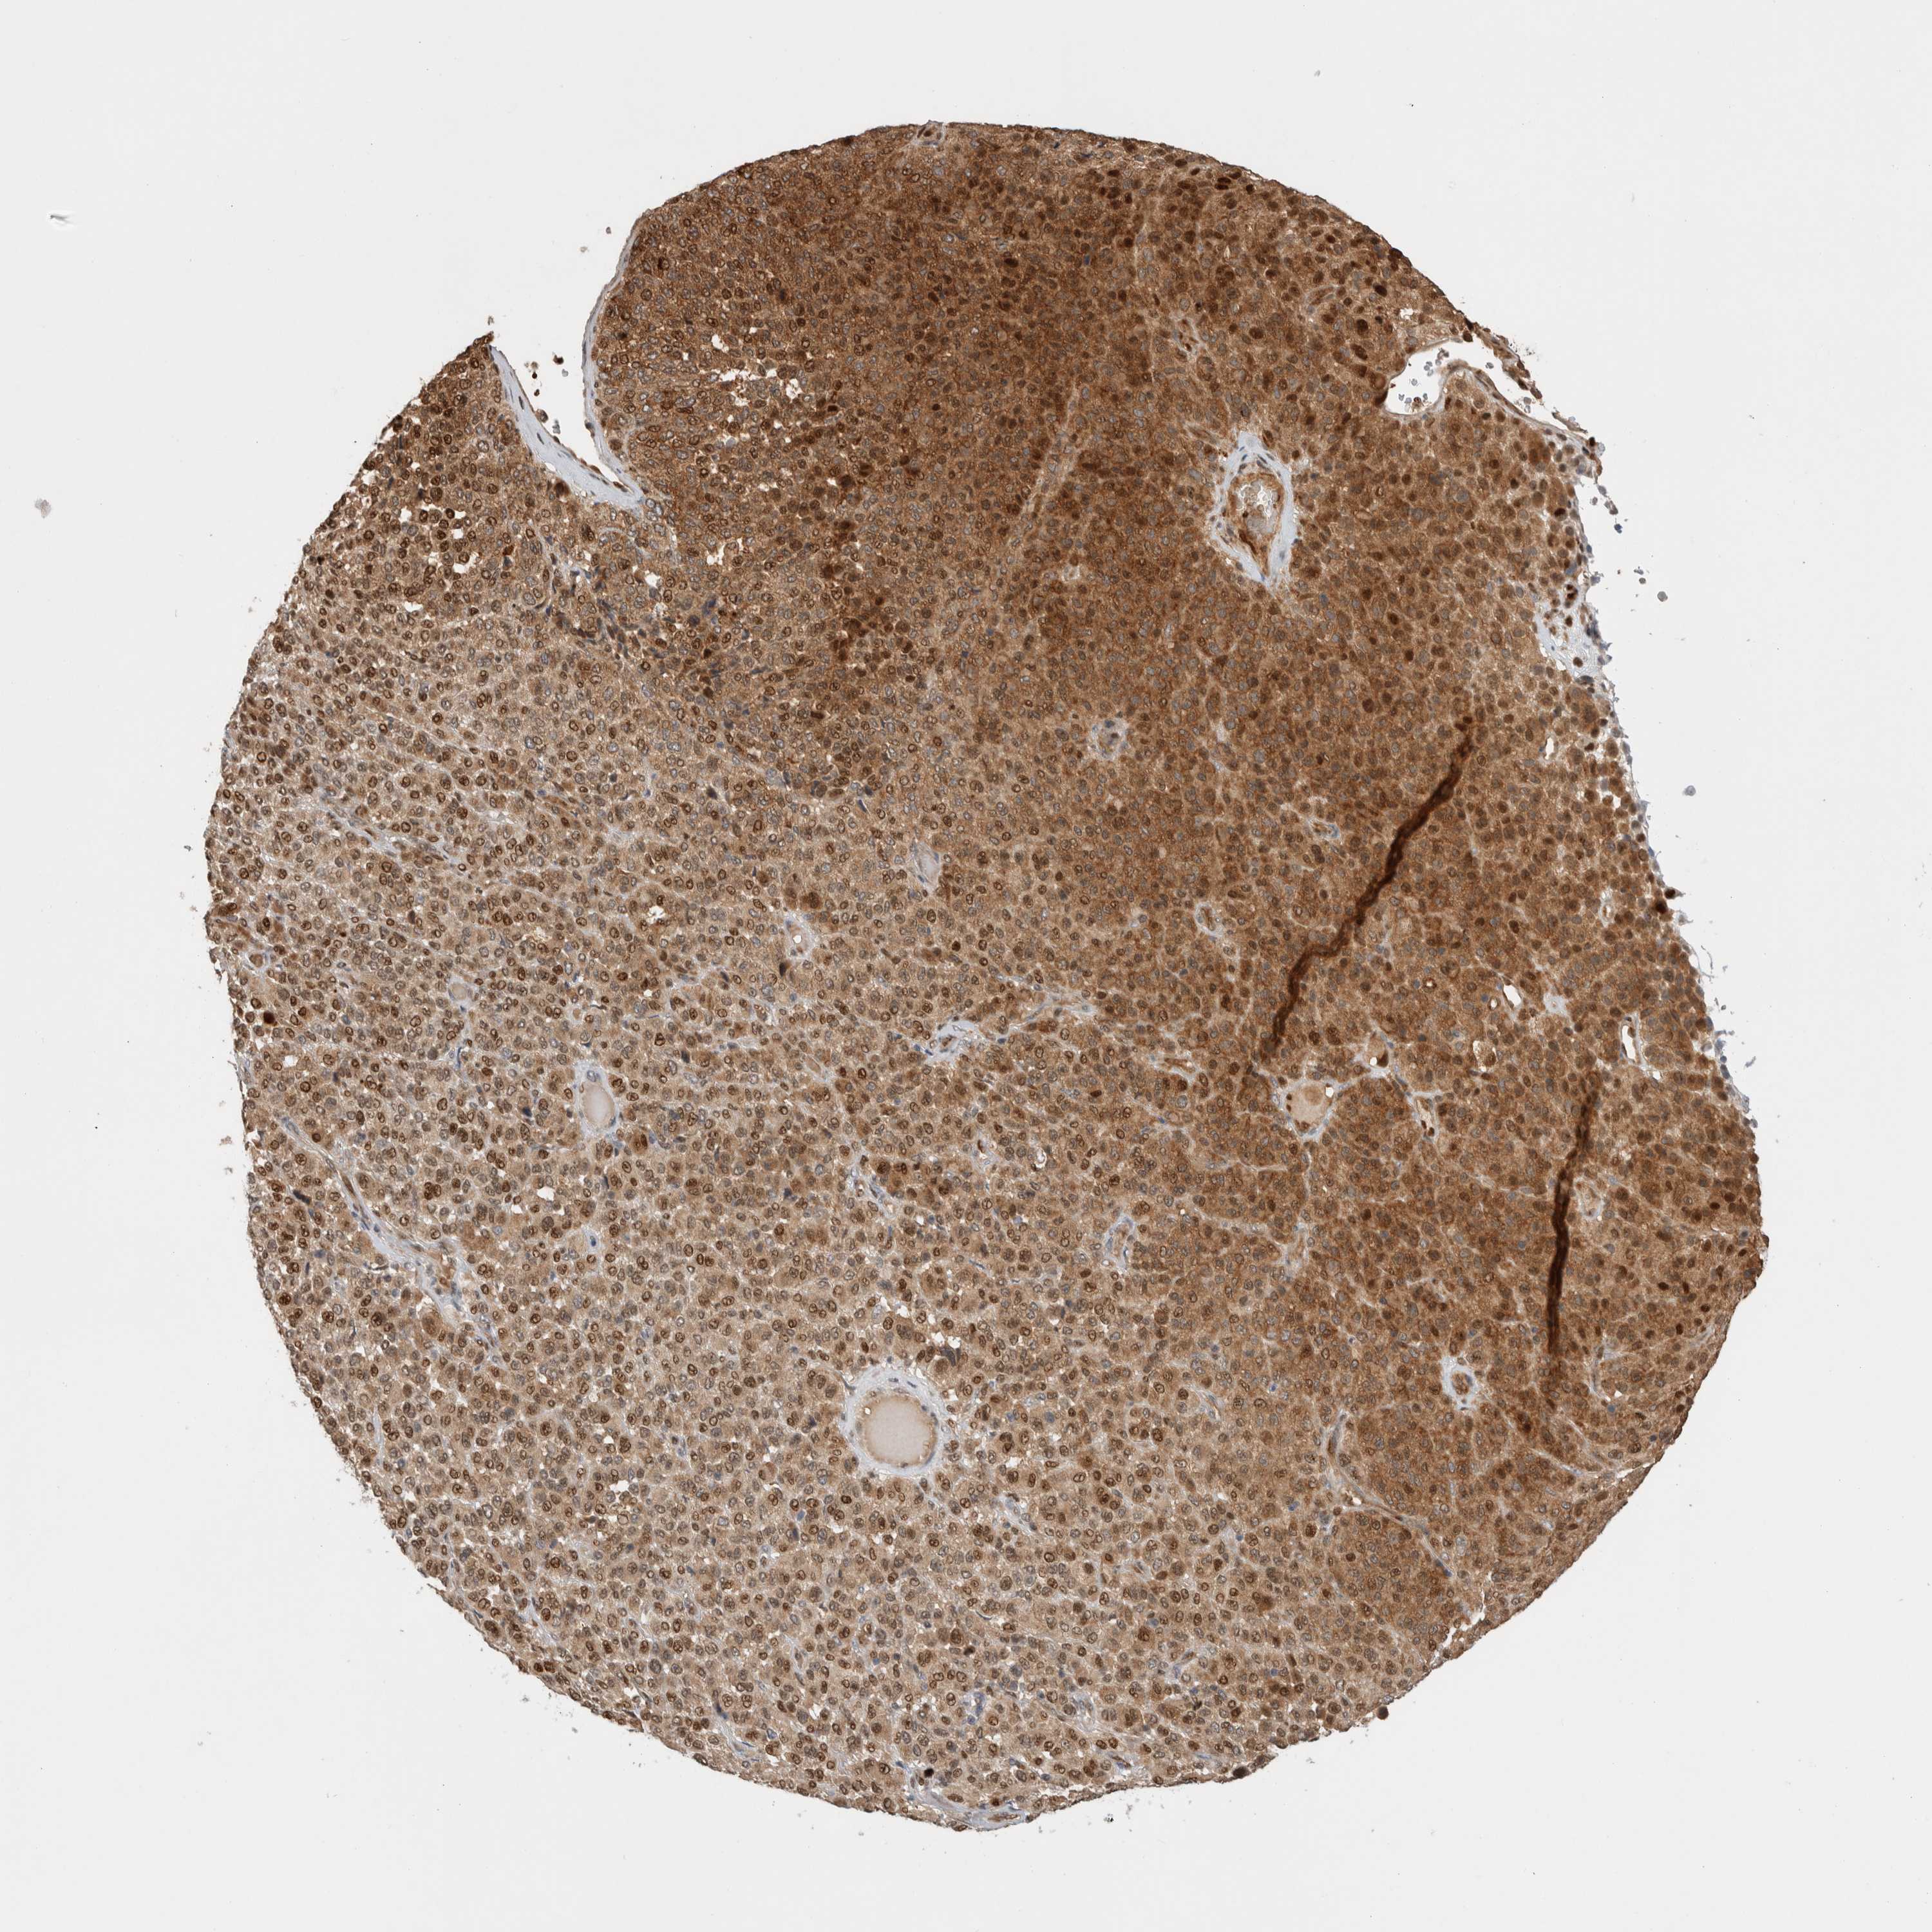

MELANOMA - Protein expressioni

A mouse-over function shows sample information and annotation data. Click on an image to view it in a full screen mode. Samples can be filtered based on level of antibody staining by selecting one or several of the following categories: high, medium, low and not detected. The assay and annotation is described here.

Note that samples used for immunohistochemistry by the Human Protein Atlas do not correspond to samples in the TCGA dataset.

Antibody stainingi

Antibody staining in the annotated cell types in the current human tissue is reported as not detected, low, medium, or high, based on conventional immunohistochemistry profiling in selected tissues. This score is based on the combination of the staining intensity and fraction of stained cells.

Each image is clickable and will lead to virtual microscopy that enables deeper exploration of all samples and also displays staining intensity scores, fraction scores and subcellular localization as well as patient and tissue information for each sample.

Antibody HPA024046

Antibody HPA024503

Antibody HPA024772

Staining

High

Medium

Low

Not detected

Intensity

Strong

Moderate

Weak

Negative

Quantity

>75%

75%-25%

<25%

None

Location

Nuclear

Cytoplasmic/membranous

Cytoplasmic/membranous,nuclear

Malignant melanoma, NOS

Malignant melanoma, Metastatic site